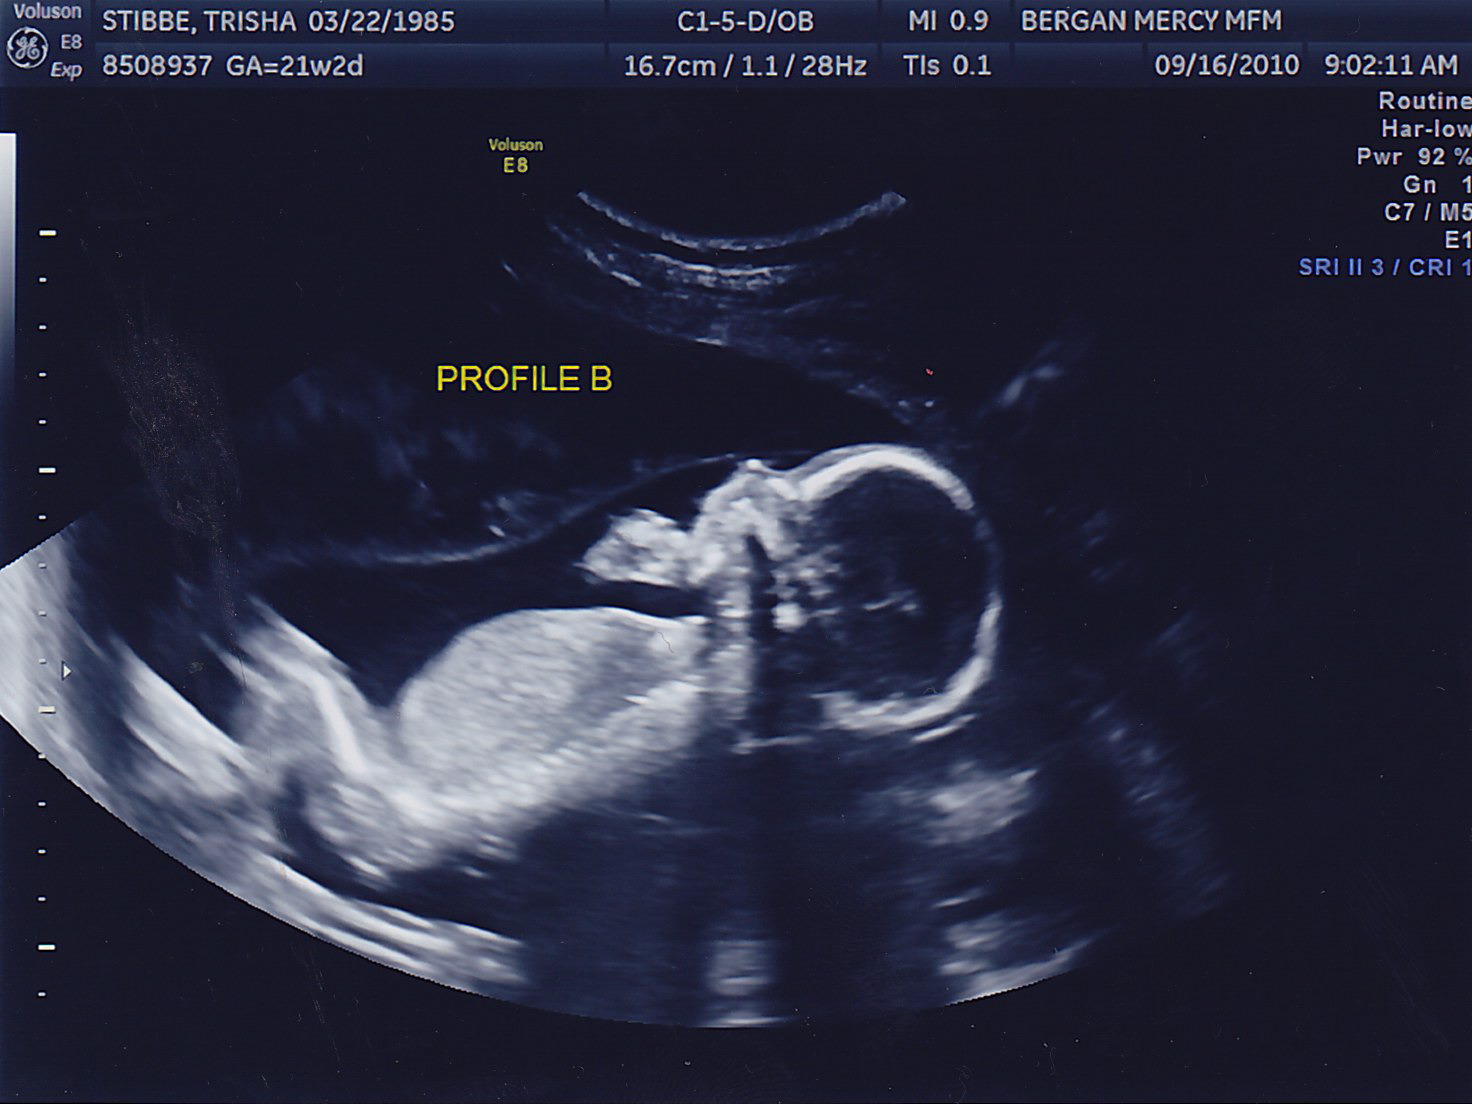

Another successful appointment! Both boys gained weight, we could see the bladder on Baby B (something the doctor needs to keep a close eye on) and the fluid levels in both looked great. No amnio therapy for Mommy today! Here are some more pictures of the little peanuts, who were called “photogenic” by the sonographer today <– very proud Mom-moment 🙂